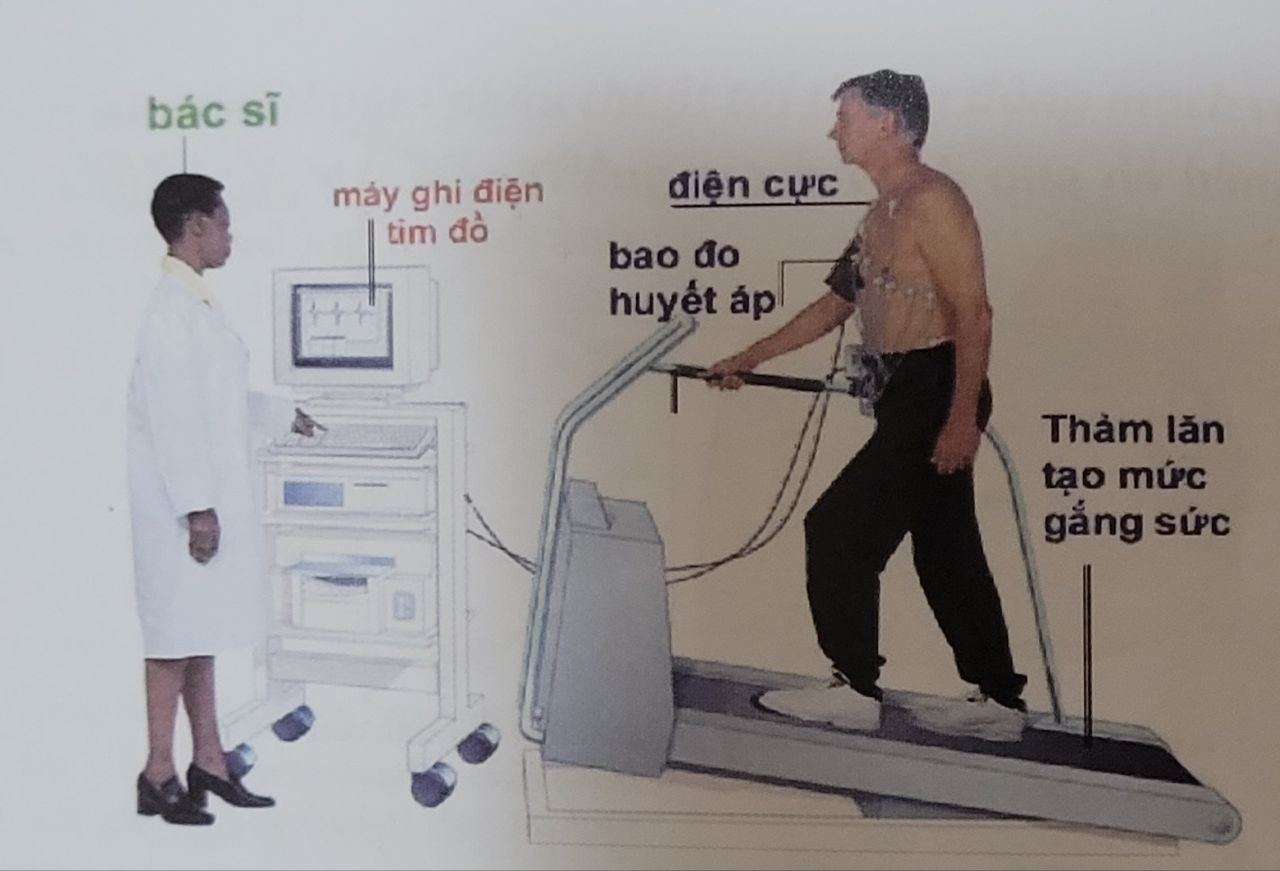

7.1. Điện tim đồ gắng sức

– Điện tim đồ được ghi nhận khi bệnh nhân gắng sức bằng cách chạy trên thảm lăn có thể điều chỉnh mức độ gắng sức, kết quả sẽ cho phân loại nguy cơ của bệnh mạch vành (thấp, trung bình, cao); trong đó, những bệnh nhân có nguy cơ cao sẽ cần chụp mạch vành và có thể can thiệp nong và đặt stent nếu tổn thương > 70% trên các nhánh động mạch vành.

Điện tim đồ gắng sức

Điện tim đồ gắng sức